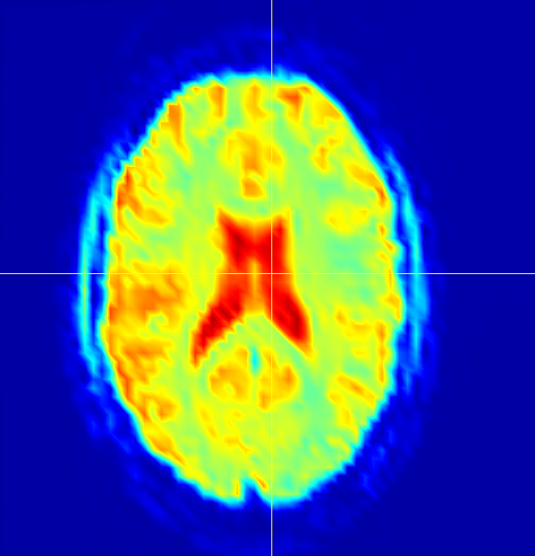

fMRI brain scan data sets are inherently four-dimensional, so unwrapping the dataset into a two-dimensional array creates a tall-skinny matrix with hundreds of times more rows than columns. The enormity of these data sets makes low-rank recovery models intractable without parallelization. Figure 11 shows the total time spent performing SPCP on one of these data sets, as well as the total time spent performing rSVDs, performing the QR step of the rSVD, and moving data (labeled as the “overhead” cost). The results of this test are included in Figures 12 and 13.

The datasets used for testing were taken from a study of the human brain’s response to uncomfortable stimuli, specifically, the feeling of submerging a hand in hot or cold water. Analyzing these scans to find common neurological responses to these stimuli is difficult due to the enormous amount of error in the data. There is uniformly distributed noise due to constant ancillary physiological activity, and there are also sparsely distributed groups representing neurological structures that should all exhibit the same behavior. The ventricles, for example, are filled with cerebrospinal fluid (CSF), which does not contribute to neurological communication, so they should not be active. All signals observed in the ventricles should be treated as sparsely structured outliers. SPCP removes the uniform noise and, most remarkably, correctly identifies signals in the brain’s ventricles as outliers. In Figure 12, the largest ventricles are the two structures in the center of the brain. The rightmost image shows that the majority of the noise contained in is from these ventricles.

The other two major components of the brain are white and gray matter. The activity we are hoping to observe takes place in the gray matter, so ideally SPCP would remove most signals from the white matter regions. However, the regions of white matter are more difficult to distinguish than the regions of CSF, and SPCP removes about equal amounts of noise from the white matter as it does from the gray. If we let be the gray-matter component of , and define and similarly, Figure 13 shows the average BOLD signal in , and for each frame in time. These data were normalized by the average original signal in the corresponding regions.

It is clear that contains more signal than the other two regions. For , SPCP detects noise in only the first 100 time slices. The removed signal from the white matter is more distributed over time, and the total amount of noise in and is comparable. These results suggest that SPCP correctly identifies outliers in the fMRI data, especially within the regions of CSF.